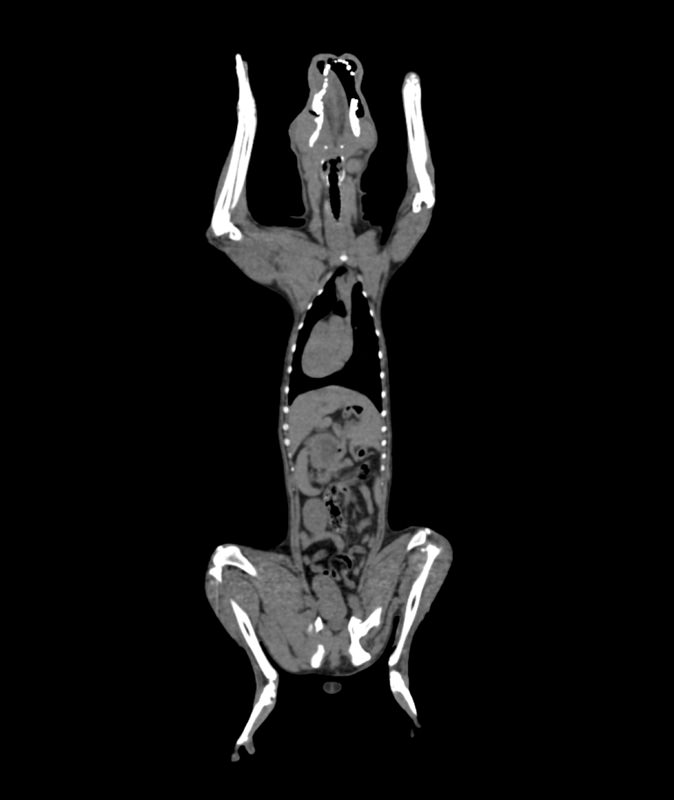

Product information “Dog phantom for CT and X-ray”

The phantom provides a realistic simulation of a dog with no contrast agent. Bones and soft tissue are displayed authentically with realistic CT values for all tissues at 120 kVp tube voltage in the CT. Air spaces are filled with a cellulose polymer composite with about -80 Hounsfield units.

Size: 26x15x80cm